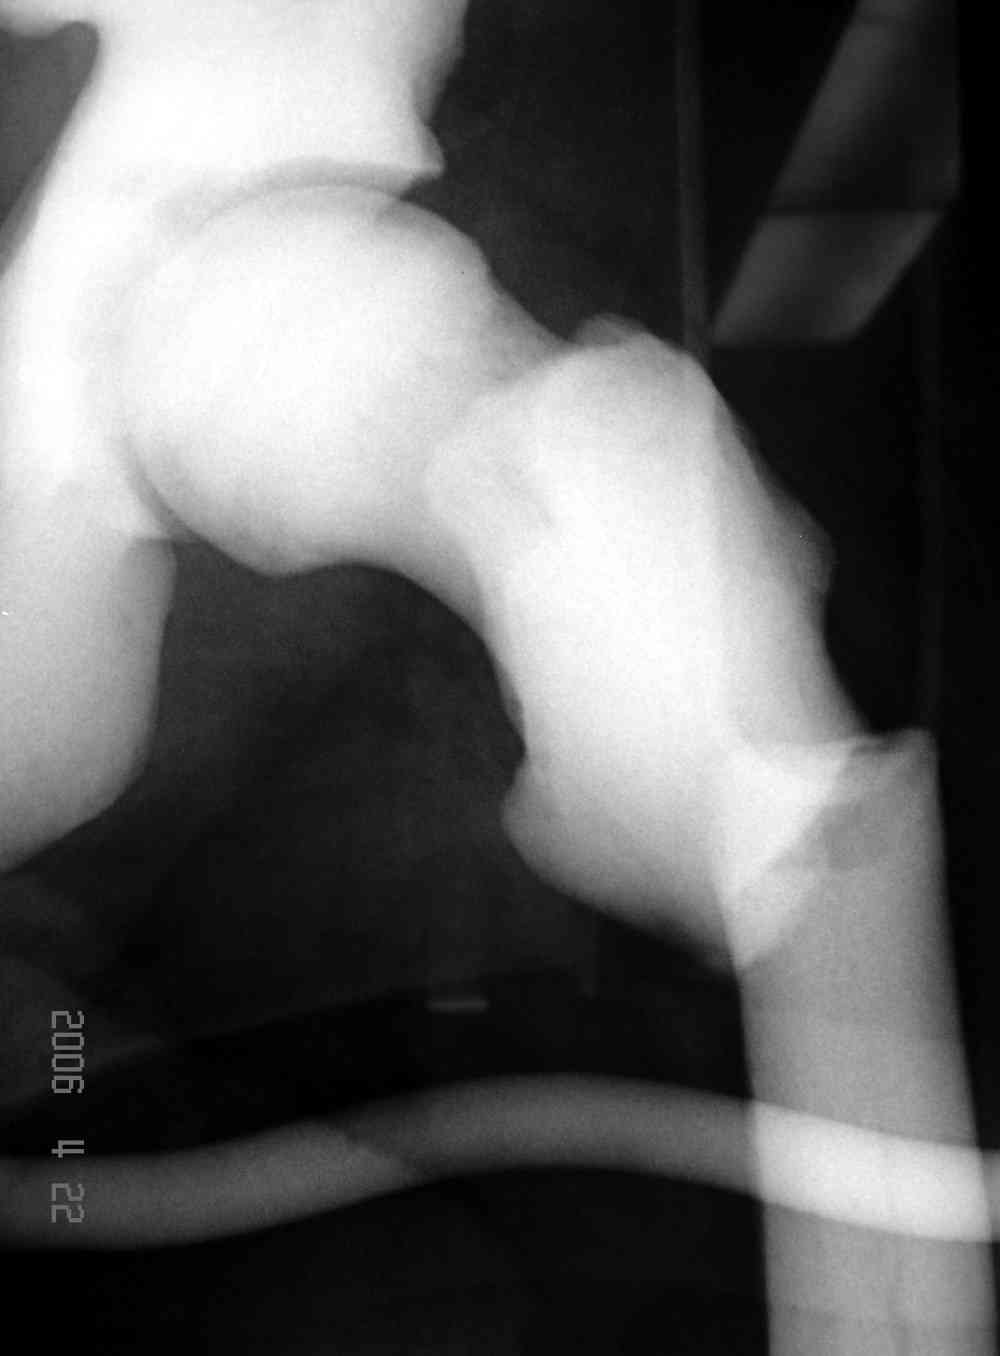

Здесь у меня дополнительные снимки с большим разрешением и в разных режимах, а то те дигитал снимки совсем очень блеклые, может, эти изображени изменят выбор тактики

Не вызывает ли подозрение, что отсутствует медуллярный канал, как просверлить канал?

Канал, возможно, действительно запаян. Но разве большие проблемы его создать и рассверлить (если только это мраморная болезн?) Уверен, в вашей клинике есть для этого всё.